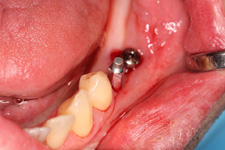

• Řízená implantace - guided surgery – statická navigace

- operace pomocí OP šablon. Ve speciálním programu coDiagnostiX se využívají data z CB CT scanu - tedy údaje o množství a kvalitě kosti, dále data získaná ze scanu modelu čelistí s modelem plánované protetické náhrady (korunky, můstku…)

- tedy údaje tloušťce sliznice, pozice a tvaru náhrady.

Tím máme všechny potřebné údaje pro plánování pozic implantátů, jejich potřebné délce a průměru. Abychom mohli implantáty zavést do naplánovaných pozic v ústech pacienta, umožňuje tento program vymodelovat speciální operační šablonu, která je zhotovena 3D tiskárnou. Pomocí této šablony, která se umístí do úst pacienta, pak probíhá vlastní operace

- zavádění implantátů.